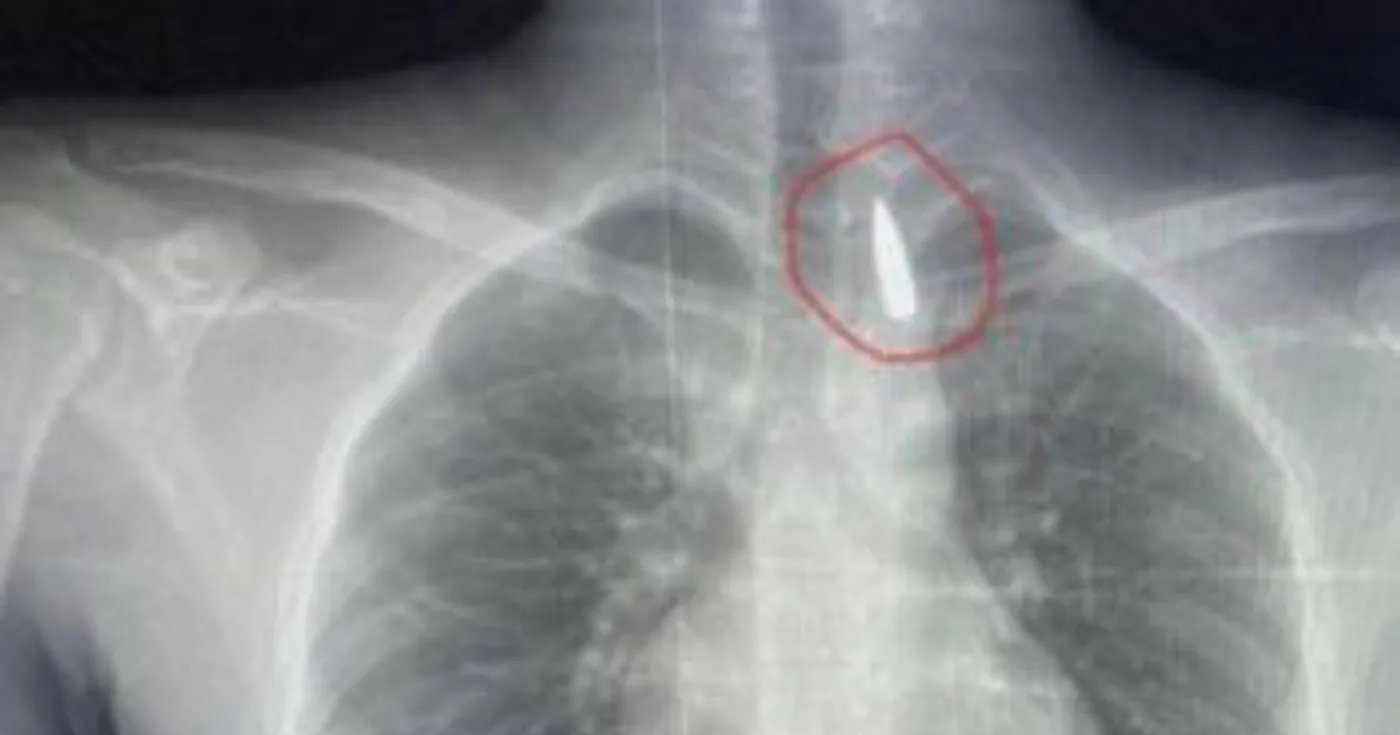

السوسنة - جريمة بشعة شهدتها منطقة دار السلام في القاهرة، ووثق فيديو مدته 52 ثانية،  إقدام شخص على قتل آخر طعنا بسلاح أبيض، في الشارع، إثر نشوب مشادة كلامية بينهما.

هذا وتلقت قوات الأمن بلاغا من الأهالي بوقوع مشاجرة بين شابين في أحد الشوارع، تطورت إلى استلال أحدهما سلاحا أبيض وتسديد عدة طعنات للمجني عليه، وأرداه قتيلا في الحال.

وانتقلت الأجهزة الأمنية، إلى مكان الواقعة في الحال، وبإجراء التحريات وجمع المعلومات ومراجعة الكاميرات الموجودة في محيط الحادث، تم رصد فيديو للجريمة مدته 52 ثانية، ظهر فيه شخصان يتشاجران، وبعدها انصرف المتهم وعاد حاملا "ساطور"، وتعدى به على المجني عليه أمام المارة بالشارع.

وعلى صعيد آخر، وثقت لقطات مصورة التقطتها كاميرا مراقبة قريبة من مسرح الجريمة تفاصيل مقتل الطالبة نيرة التي تم ذبحها بسكين من قبل زميلها أمام المارة على بوابة الجامعة، وسجلت اللقطات زاوية جديدة كشفت التفاصيل الكاملة للجريمة وعدد الطعنات التي سددها المتهم محمد للطالبة، وبلغت عدد الطعنات التي وجهها المجرم للضحية 13 طعنة، كما قام بنحرها مرتين، وفي التحقيقات أكد شهود العيان رؤيتهم المتهم أثناء ارتكابه الجريمة.